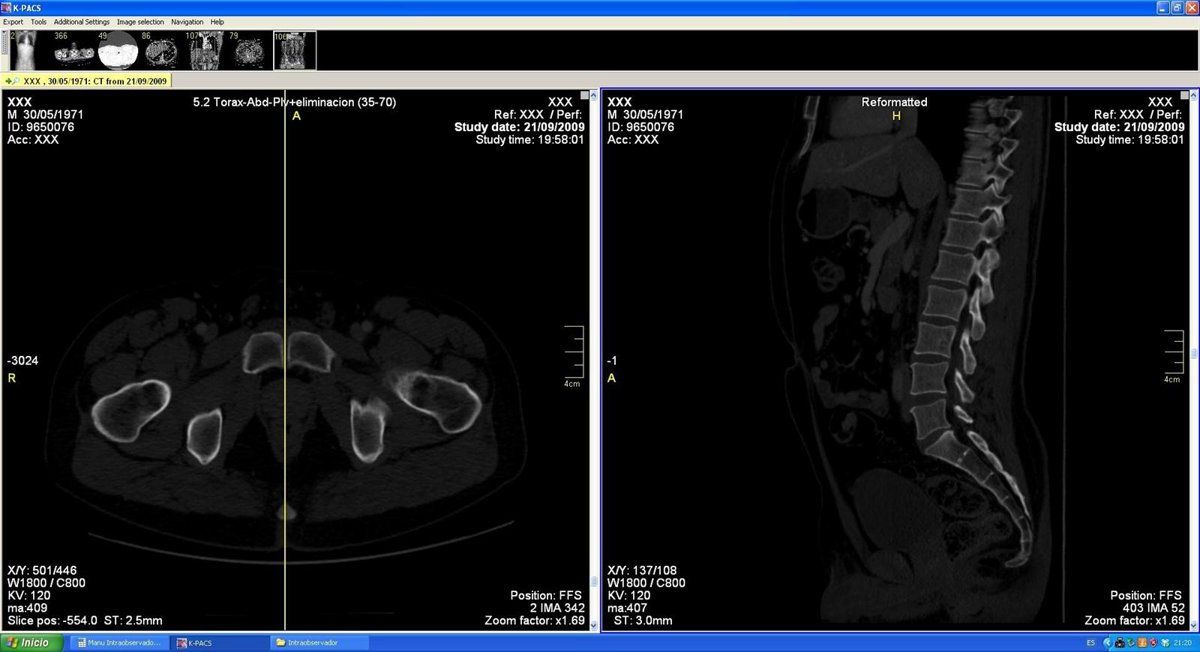

Ejemplo de selección del corte de estudio.

En estos estudios se identificaron los cortes sagitales de la superficie articular sinfisaria y del cuerpo del pubis, de manera que de cada estudio se obtuvieron un total de cuatro cortes: dos de cada superficie articular sinfisaria derecha e izquierda y otros dos de cada cuerpo del pubis.

Dichos cortes se analizaron mediante técnicas de imagen, extrayendo el histograma de dichas estructuras, utilizando el programa Imagen y utilizando variables estadísticas de los histogramas para ponerlos en relación con la edad y el sexo.